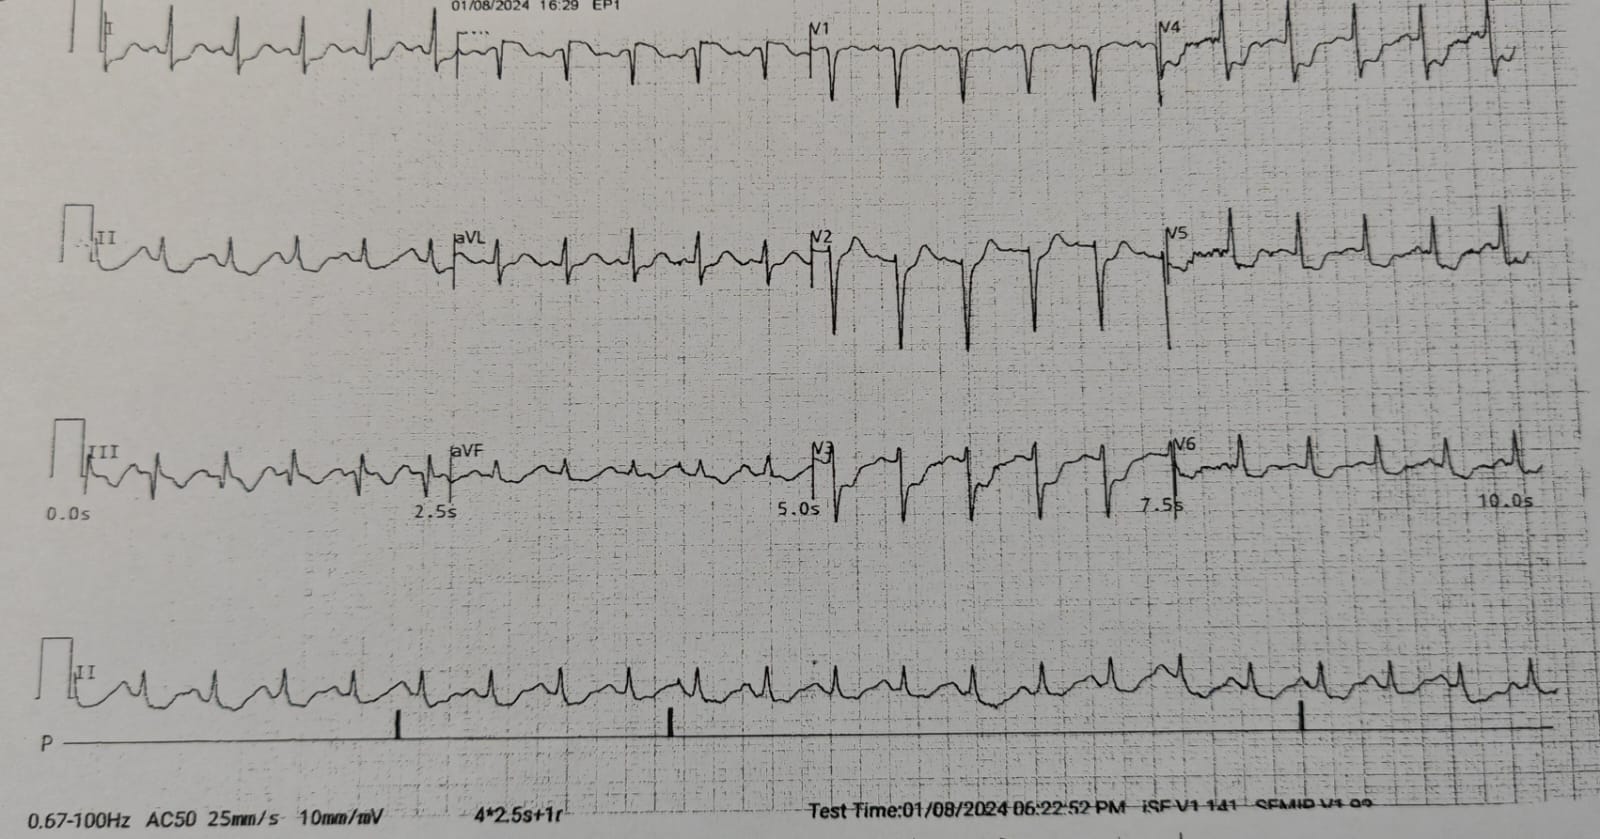

TnI : 8507 ng/LECG: SR STE aVR, diffuse ST depression